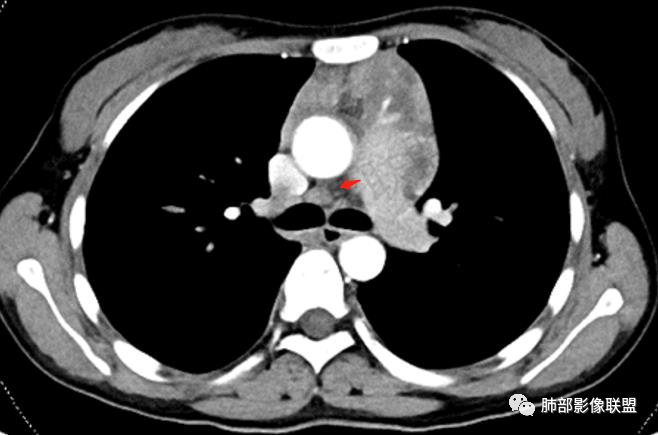

2.影像显示前纵隔不规则块状影,依势贴附心脏大血管旁,密度不均,边界不甚清楚,有结节融合感。

3.病灶轻度不均匀强化,可见血管穿行,散在液性低密度区。

双肺门未见肿大淋巴结。

4.双侧腋窝区见增大淋巴结,边界清楚。

1.年轻女性,前纵隔不规则块状影,密度不均,边界不甚清楚,有结节融合感,轻度不均匀强化,可见血管穿行,最常见最符合的无疑是淋巴瘤!

前纵隔和双侧腋窝多发的淋巴结肿大,前纵隔为甚,融合呈中等强化,部分坏死呈低密度,包埋肺动脉主干和左心缘,融合斑块状,内见血管飘浮特点,前纵隔脂肪间隙混浊,首选淋巴瘤!